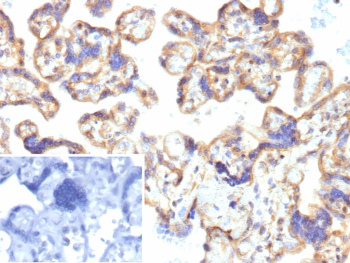

IHC analysis of ENTPD1 Antibody in FFPE human placenta tissue. The recombinant mouse monoclonal antibody (clone r22A9) demonstrates membranous HRP-DAB brown staining in trophoblastic cells lining chorionic villi, consistent with CD39 / ENTPD1 expression, while background stromal elements show minimal staining. The inset shows PBS used in place of the primary antibody as a secondary-only negative control. Heat-induced epitope retrieval was performed in 10mM Tris with 1mM EDTA, pH 9.0, at 95oC for 45 minutes followed by cooling at room temperature for 20 minutes.